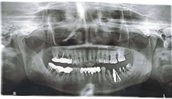

Figure 4: OPG [1 zirconia implant placed in #27] and clinical photograph

Figure 6: OPG of the same patient 1 zirconia implant placed in #47